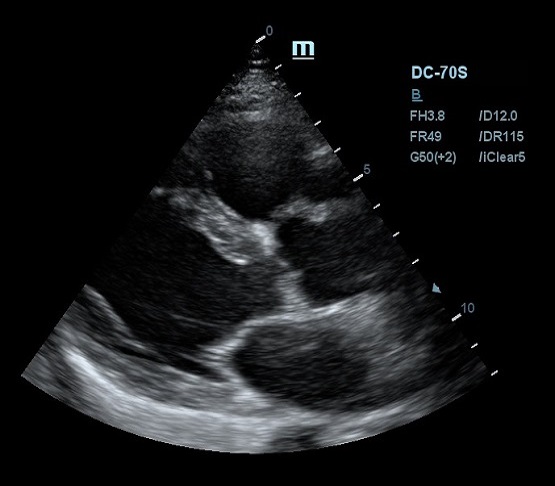

Благодаря постоянным инновациям, компания Mindray внедрила технологию iClear (адаптивная обработка изображений). Спекл - артефакт визуализации в виде акустического пятна - был препятствием для дифференциации структуры исследуемой ткани. iClear реализует агрессивное подавление спекл-паттернов, позволяя четко визуализировать анатомическую структуру на ультразвуковых изображениях. За счет уменьшения спекл-шума достигается лучшая дифференцировка тканей. Повышается контрастное разрешение без ущерба для пространственного разрешения. Уровень подавления спеклов можно выбрать под свои задачи, достаточно нажать кнопку или повернуть ручку, остальное сделает программный алгоритм.

Другим важным нововведением в постобработке ультразвукового изображения является система EchoBoost. Ткани миокарда отражают различные по интенсивности ультразвуковые волны, и при обработке их одним потоком качество изображение оставляет желать лучшего. Технология EchoBoost позволяет прибору производить анализ эхо-сигналов разной интенсивности индивидуально, создавая затем четкую картинку.

Прибор также обрабатывает каждую область исследуемого региона отдельно, учитывая особенности распространения ультразвуковой волны. В связи с тем, что ультразвуковая система рассматривает низкоинтесивные колебания отдельно, имеется возможность усилить слабое эхо и отделить его от шума. Таким образом сонограмма становится более детальной и четкой, что очень критично в эхокардиографии.